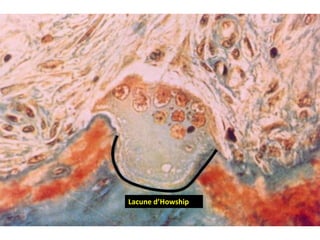

d- Ostéoclastes : (suite)

• Liaison à la matrice organique par les intégrines

• Délimitant une zone étanche sous la bordure en brosse :

chambre de résorption ou lacune de Howship

• Une zone claire : pauvre en organites mais possédant de

nombreux filament d’actine est présente tout autour du dôme

au niveau de la zone de contact avec la matrice minéralisée

Lacune d’Howship

• Processus de résorption osseuse :

 nombreuses pompes à protons

 consommation d’ATP et d’enzymes

• Anhydrase carbonique de type II production de protons  expulsés par

les pompes à protons membranaires ATP-dépendantes sous la bordure en

brosse libération de protons H+  chute du pH dissolution de la phase

minérale  un environnement optimal pour l’activité enzymatique 

ostéoclaste libère nombreuses enzymes lysosomales  dégradation des

éléments de la matrice organique  formation de la lacune de Howship